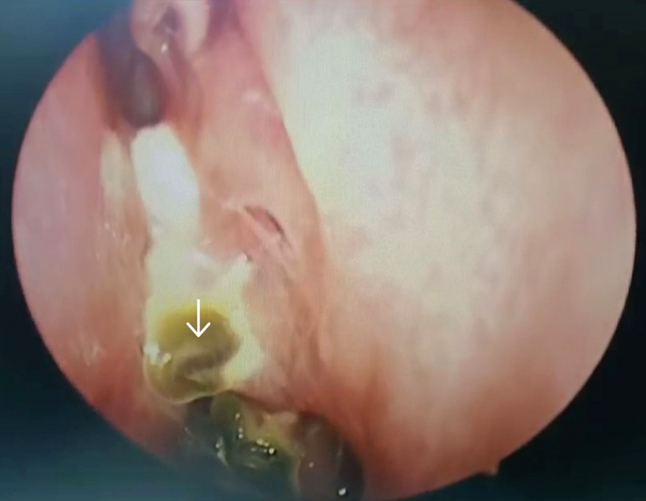

The meningoencephalocele was reduced by bipolar cauterization, the sphenoid sinus mucosa removed, the defect was closed by insertion of fat harvested from the left thigh (figure 7), followed by artificial dura, fascia lata harvested from the left thigh, followed by tissue glue and by another layer of fascia lata (figure 8). The defect in the cribriform plate was cauterised and sealed with fat and fascia lata harvested from the left thigh and subsequently reinforced with tissue glue and gel foam (figure 9).

Figure 7. Arrow showing the fat being placed on top of the sealed defect of the left lateral recess of sphenoid